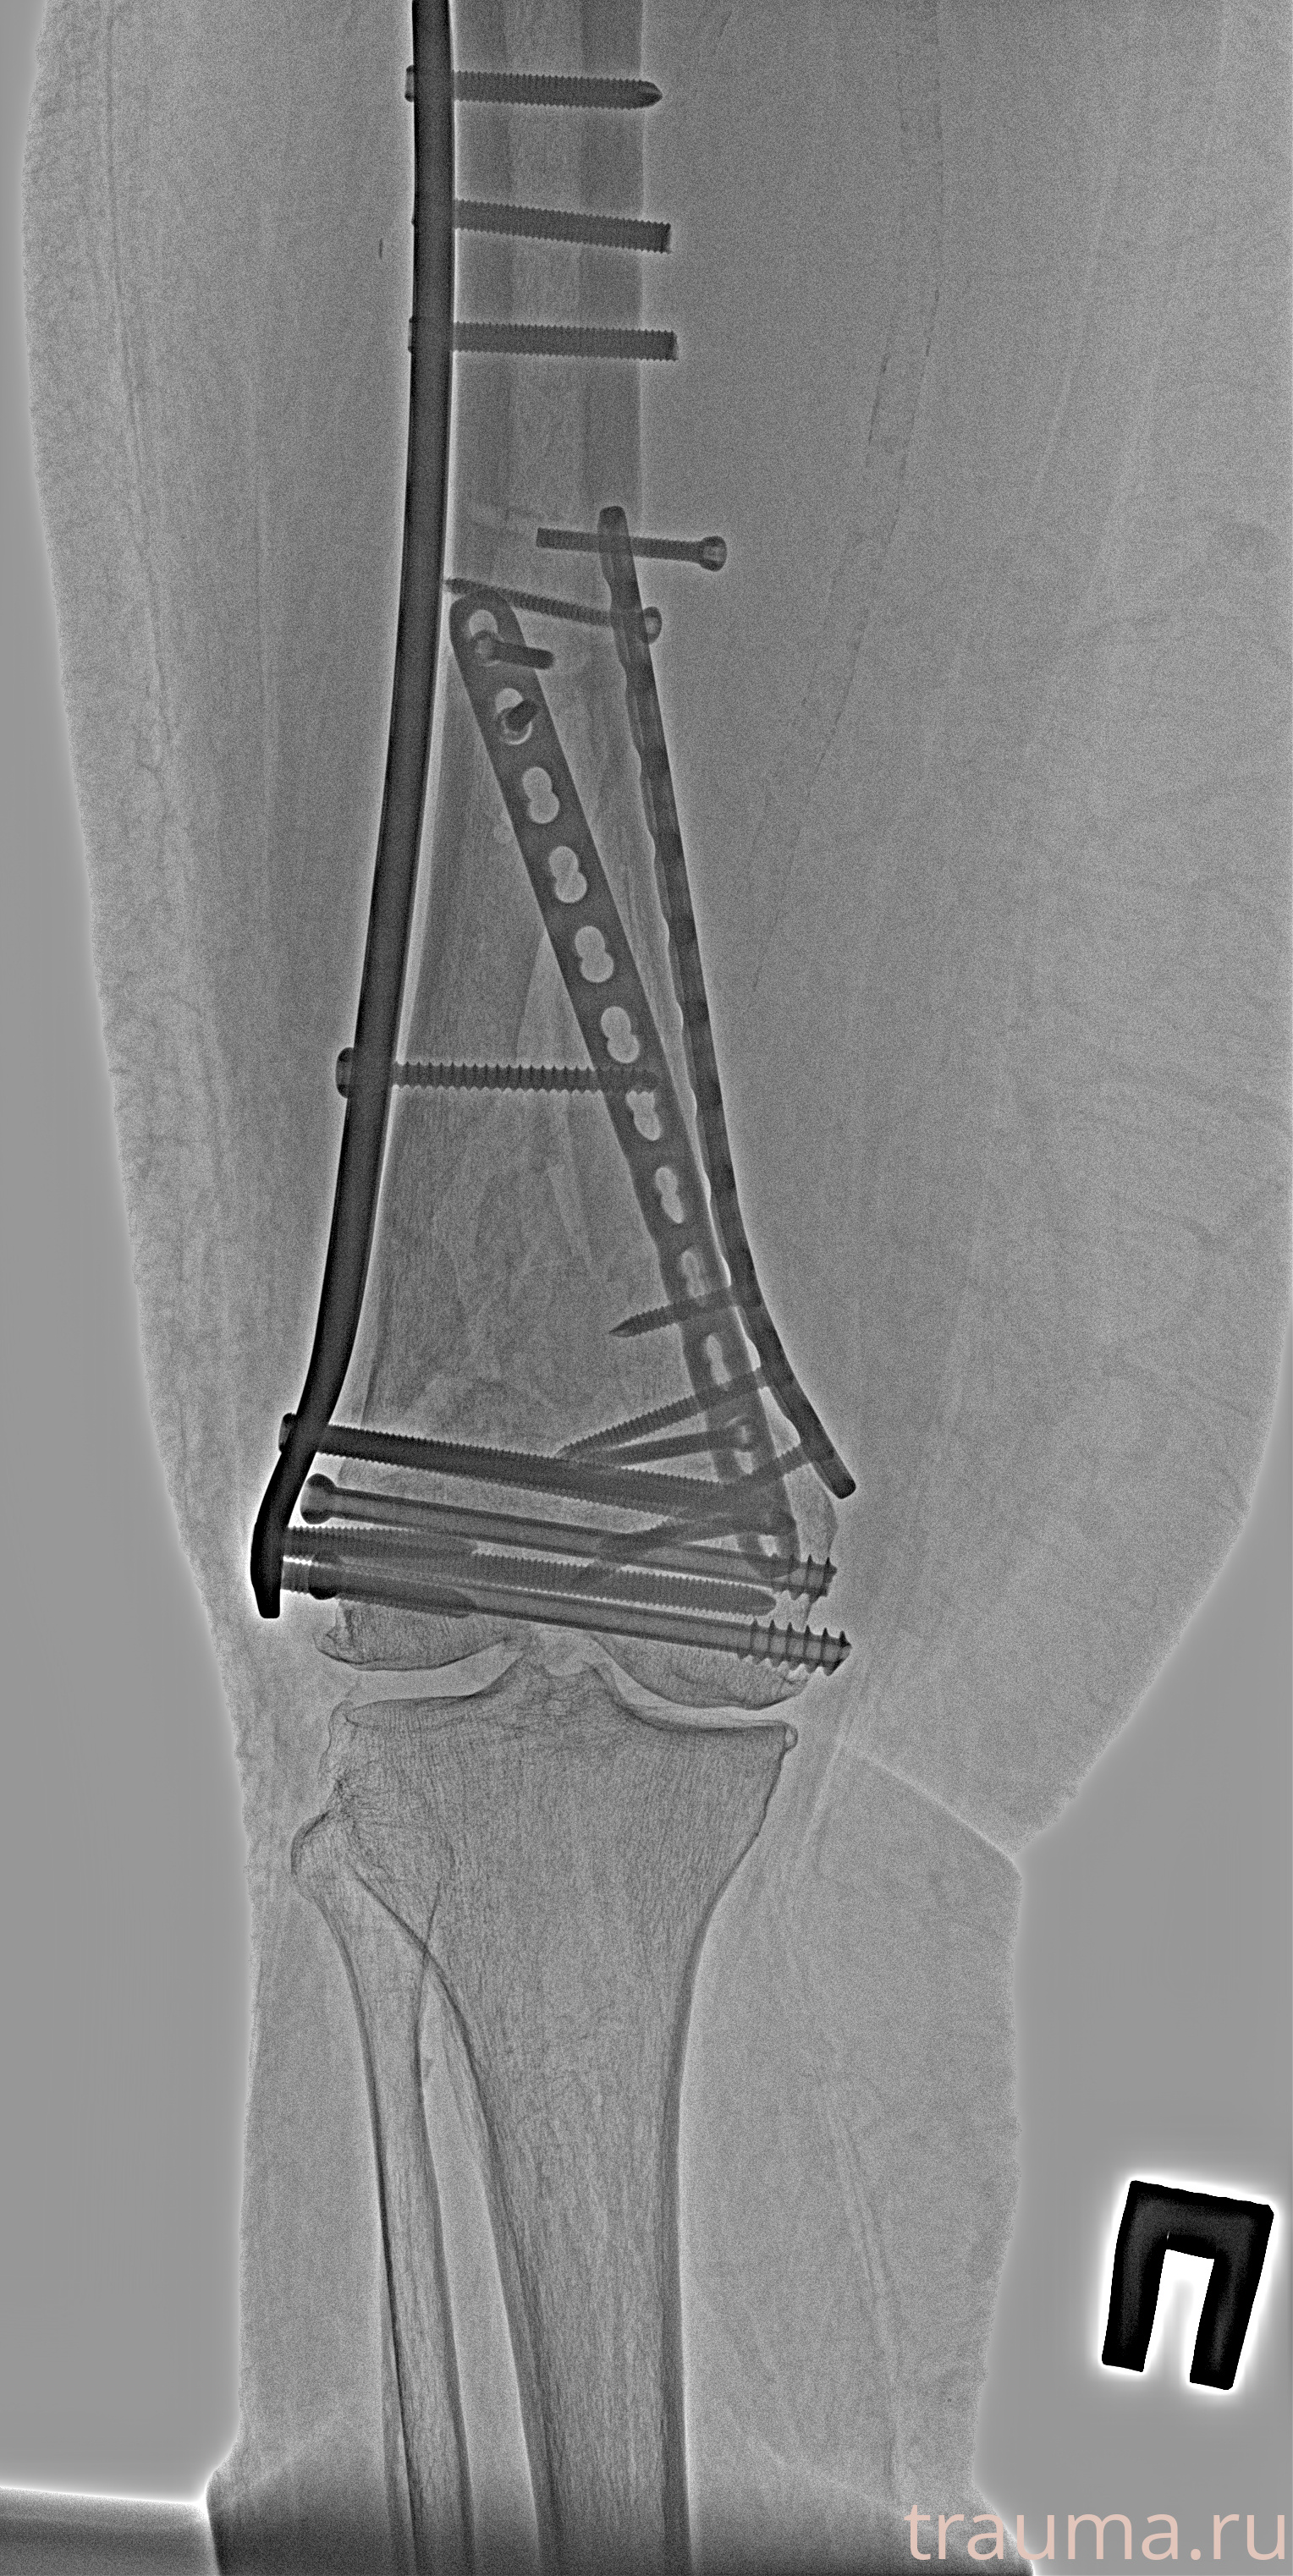

Рентгенограммы